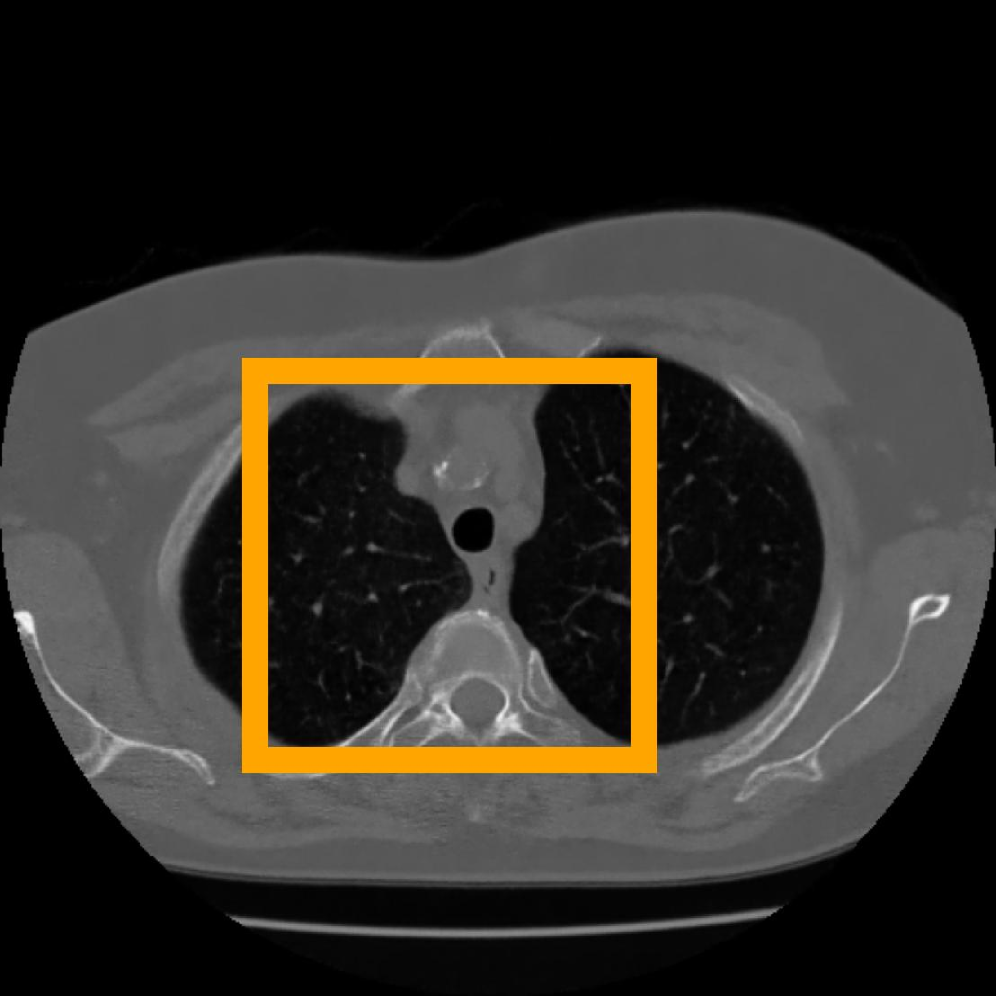

In addition, we use the CT Heart Segmentation dataset [NikhilTomar], which contains a series of 2D computed tomography (CT) heart scans with the resolution of 512 ×\times 512. This dataset provides clear anatomical structures of the human heart, and is widely used in medical image segmentation and compression tasks. Its inherent slice-based nature naturally aligns with our patch-based INR compression strategy, allowing us to further evaluate the effectiveness of COLI for medical images with rich structural information.

Figure 10: The visual comparison of different compression methods on a CT Heart Segmentation image.

Figure 11: Zoomed-in view of the highlighted region in Figure 10.

IV-B3 Visual Comparison

Figures 7 and 8 present representative examples from the CIL dataset and their zoomed-in regions, respectively. For the CT Heart Segmentation dataset, Figures 10 and 12 illustrate typical reconstruction results, while Figures 11 and 13 further enlarge local regions to compare structural details. Across both datasets, COLI preserves fine structures and global continuity well even at relatively low bpp. Specifically, on the CIL dataset, COLI attains the lowest bitrate among INR-based methods while still maintaining clear texture details. On the CT Heart dataset, COLI also operates at a low bpp within the INR family and delivers superior visual quality with improved detail fidelity and smoother structural presentation. The zoomed-in regions show fewer blocking artifacts and smoother transitions, making COLI especially suitable for large images and medical images. These visual results validate that INR-based compression can achieve efficient storage with reliable perceptual consistency, offering practical advantages for real-world large-scale image processing.